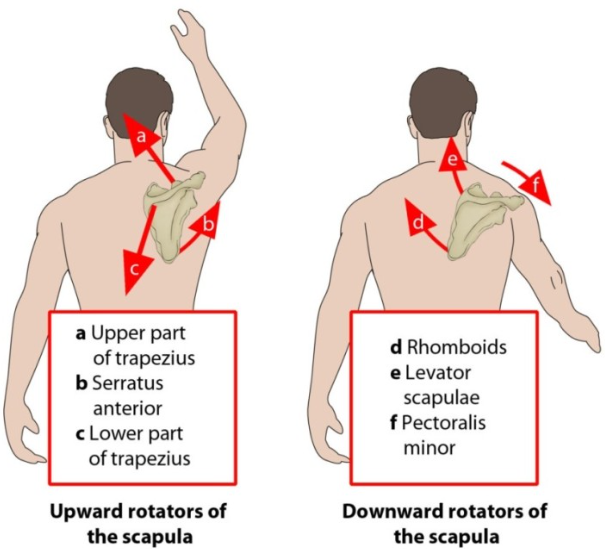

ㆍ상방회전(Upward rotation) / 하방회전(Downward rotation)

가장 흔한 이유로서 견갑골의 안정화를 도와주는 근육들의 문제가 있을 때 발생됩니다. 이러한 역할을 도와주는 근육들은 상부승모근, 전거근, 하부승모근, 능형근, 견갑거근, 소흉근이 작용해줍니다.

이중에서 전거근과, 하부 승모근은 견갑근에 내측끝에 위치해서 상방회전하면서 팔의 외전동작에서 중요한 역할을 합니다.

전거근과 승모근은 견갑골의 안정화에 매우 중요한 근육입니다. 특히 이 근육들은 상지 운동을 할 때 함께 작용하고, 특히 머리쪽으로 손을 올리는 동작들(Overhead position)에서 중요하게 작용합니다.[47][48] [49]

또한 운동이상증을 일으키는 주요 근육이기 때문에 [16] 재활 시 중요합니다.

어깨를 으쓱하는 운동은 상부, 하부 승모근을 활성화하고 상방회전의 회전각도를 증가시킵니다.

따라서 이 운동은 견갑골 이상운동증환자중에서 견갑골 하향 회전 증후군 환자에게 유용합니다.